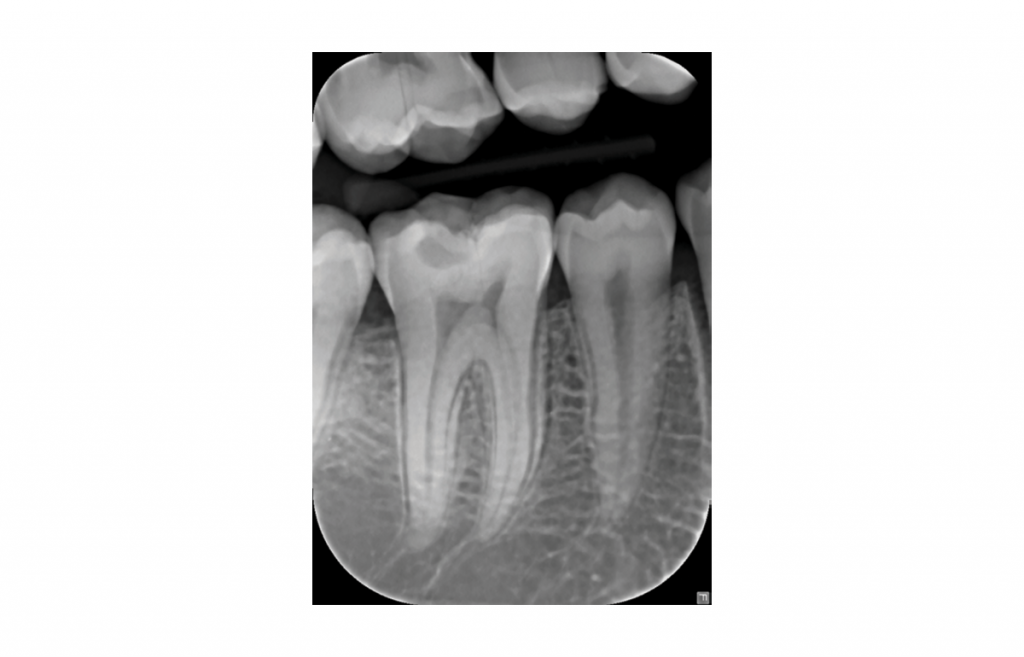

Intraoral X-ray – that’s always close to the patient

The accurate KaVo FOCUS X-ray generator technology ensures safe exposure and repeatable image quality at all times.

- Consistent images

Predictable results